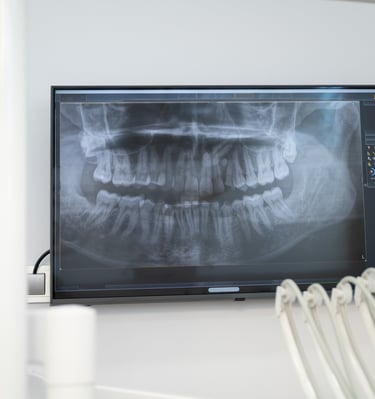

A avaliação endodôntica combina exame clínico, radiografias e análise de sintomas. Essa etapa é fundamental para identificar:

1. Diagnóstico Preciso.